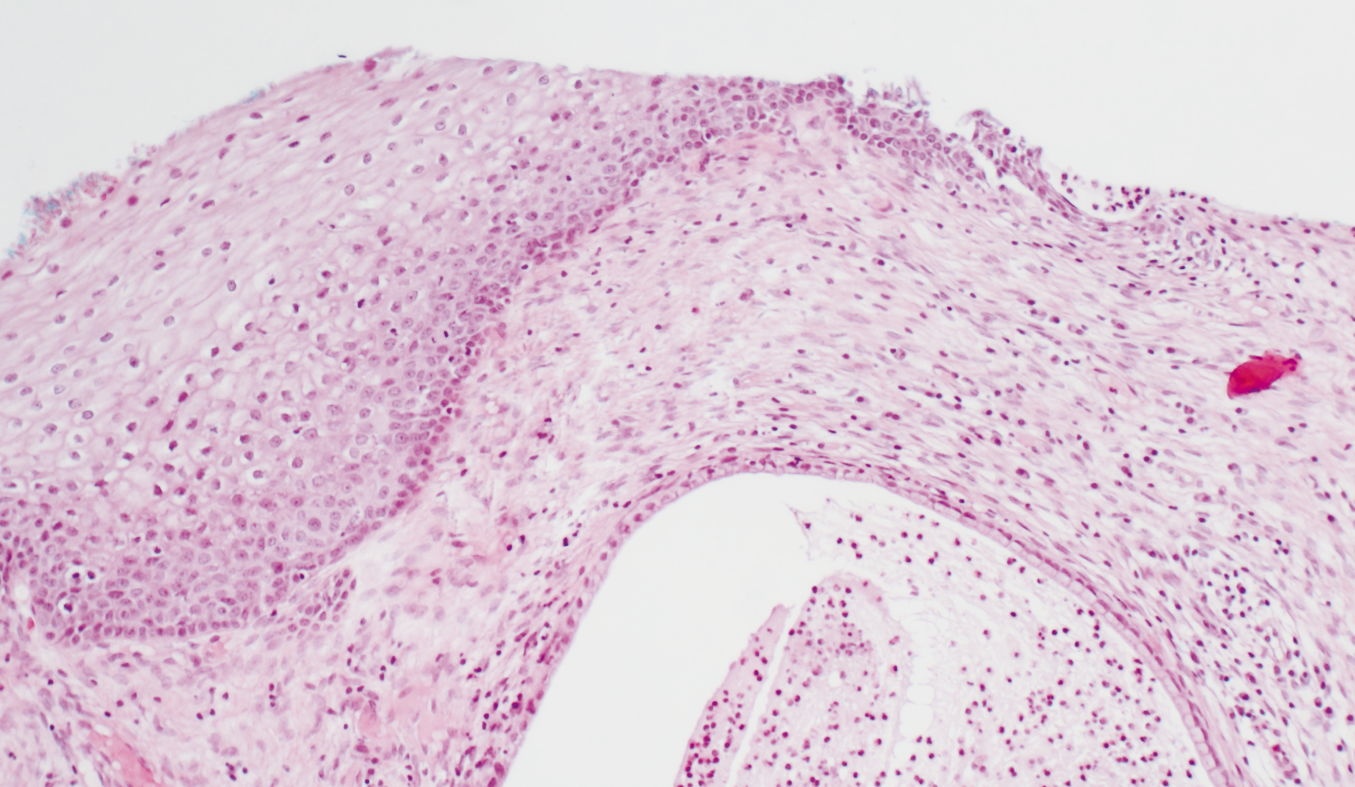

Normal non-keratinizing squamous and columnar epithelium. H&E